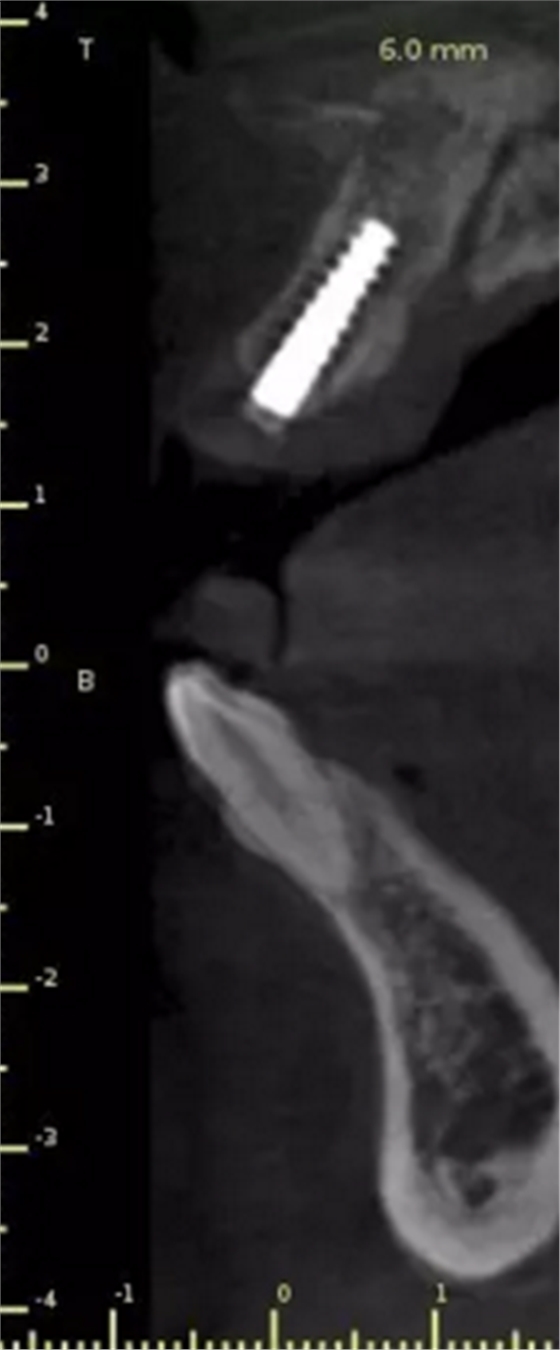

頜面部消毒→鋪襟→局麻下翻瓣→帶入導(dǎo)板→定位鉆定位→擴(kuò)孔鉆擴(kuò)孔→植入3.0x13植體→覆蓋螺絲→縫合→沖洗→術(shù)后醫(yī)囑

術(shù)后CT